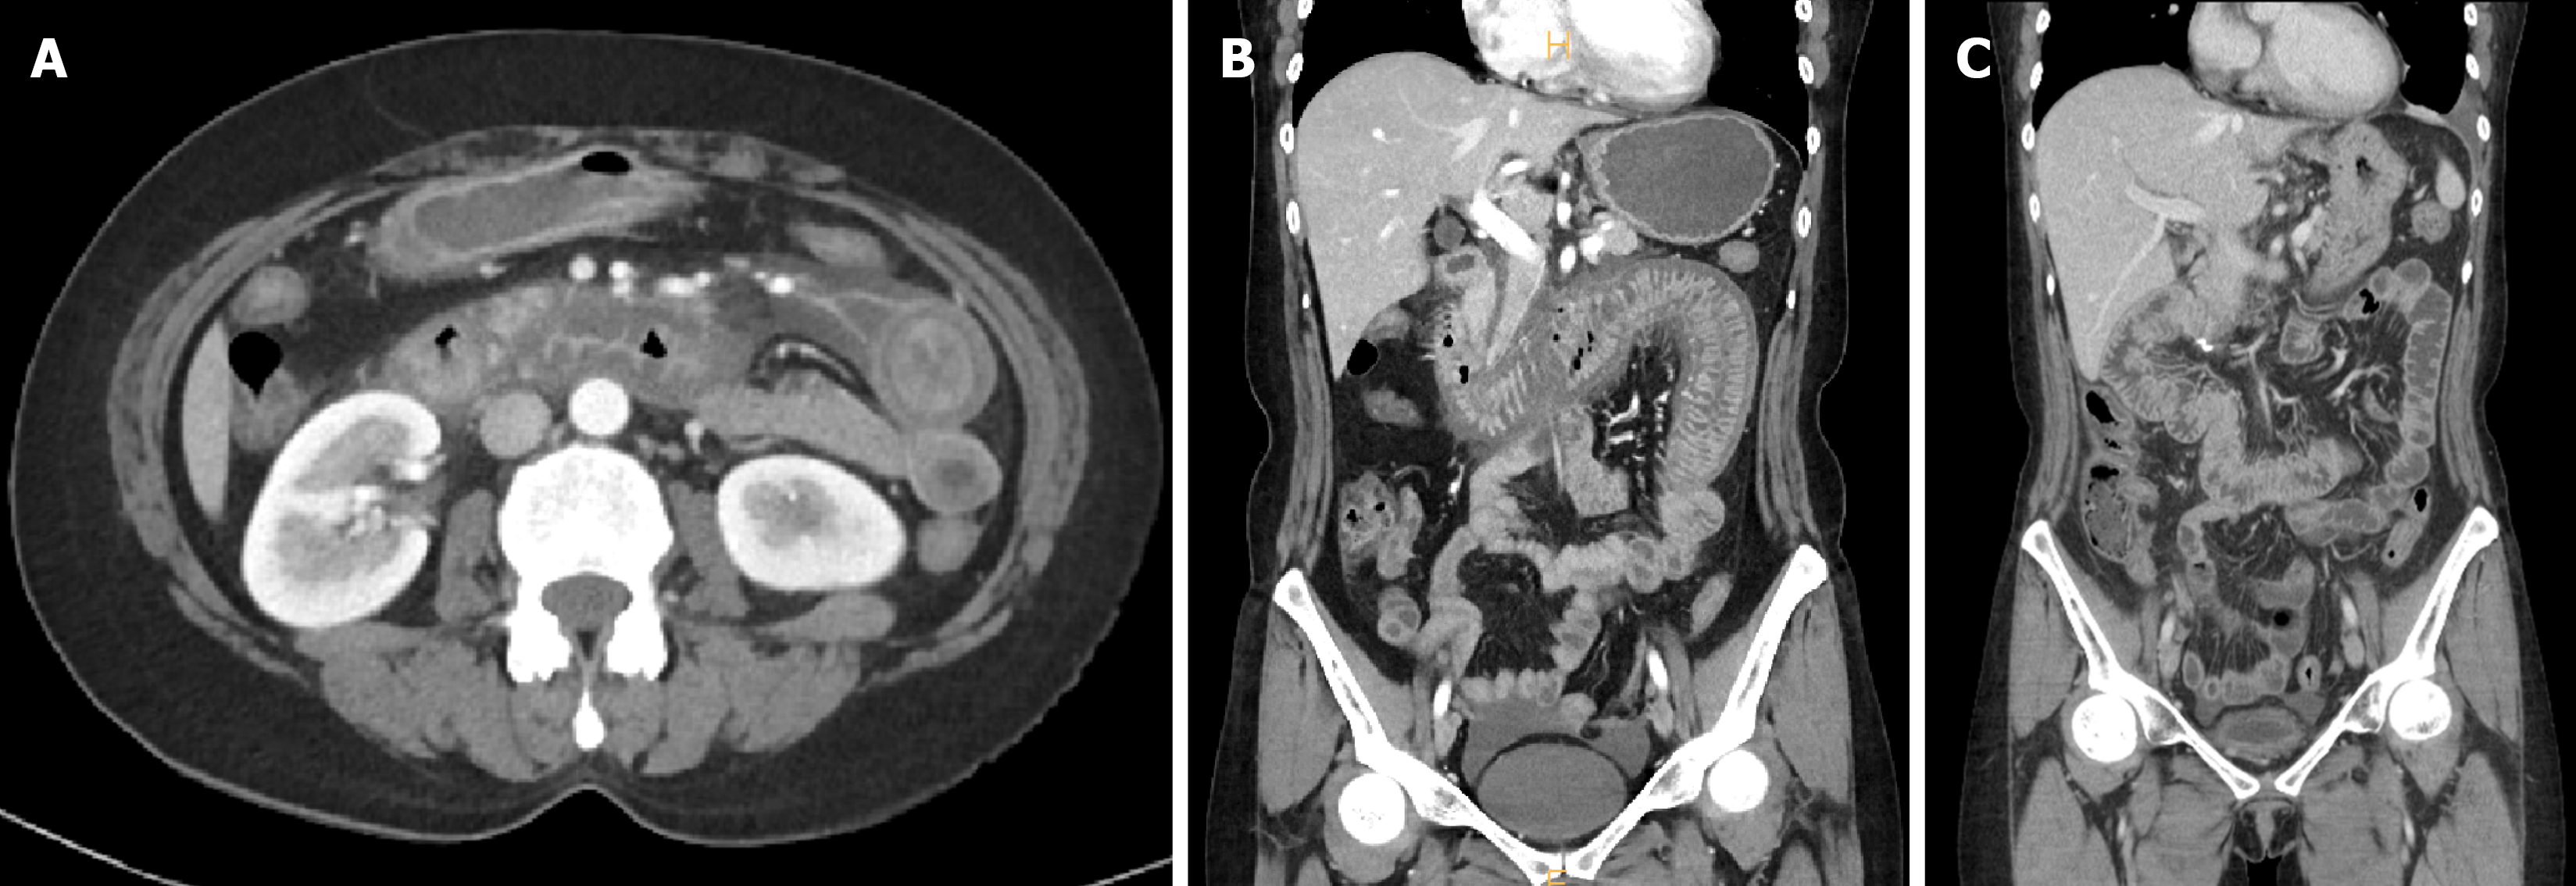

Abdominal contrast-enhanced CT demonstrated circumferential wall thickening and mucosal hyperenhancement involving approximately 50 cm of small bowel from the second portion of the duodenum to the proximal jejunum, with surrounding mesenteric fluid and engorged mesenteric veins (Figure 2A and B).

No occlusive lesion was detected in the superior mesenteric artery or vein, suggesting venous ischemia rather than arterial obstruction. These findings are consistent with previously described radiologic features of lupus enteritis, where venous congestion and submucosal edema predominate[6-8].